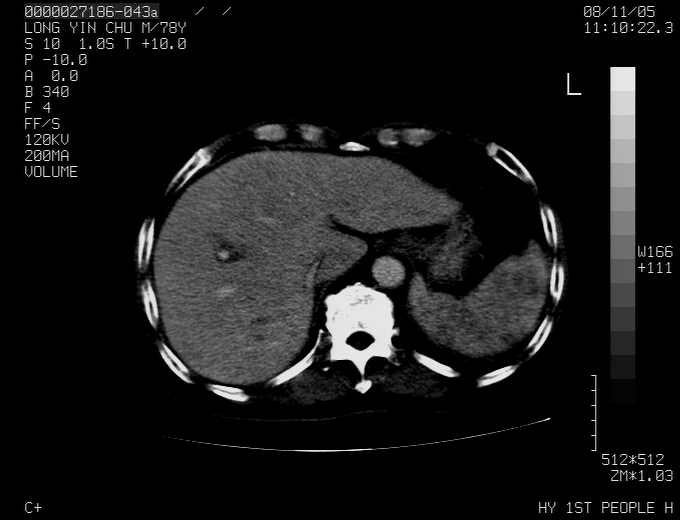

标题: CT16532:M78Y,肝脏病变,请会诊 [打印本页]

标题: CT16532:M78Y,肝脏病变,请会诊

腹胀,腹痛就诊,男性,78岁,外院b超未见异常。

肝ca,脾肾转移

支持脾肾转移瘤,双侧胸腔积液。

考虑弥漫性肝癌并脾及双肾转移.双侧胸水.

图片质量欠佳:多考虑:左侧肾癌。脾脏转移!胸膜转移!

考虑弥漫性肝癌并脾及双肾转移.双侧胸水.  支持

肝脾肾转移瘤可能性大,左肾不除外梗塞,双侧胸水

考虑弥漫性肝癌并脾及双肾转移,双侧胸水。

考虑肝癌并双肾及脾脏转移;双侧胸腔积液。